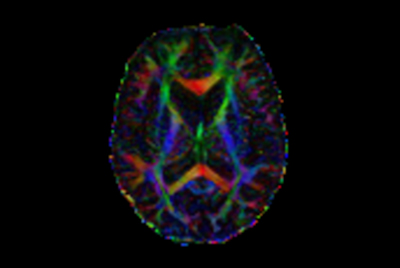

Comprehensive Brain with MultiBand SENSE DTI